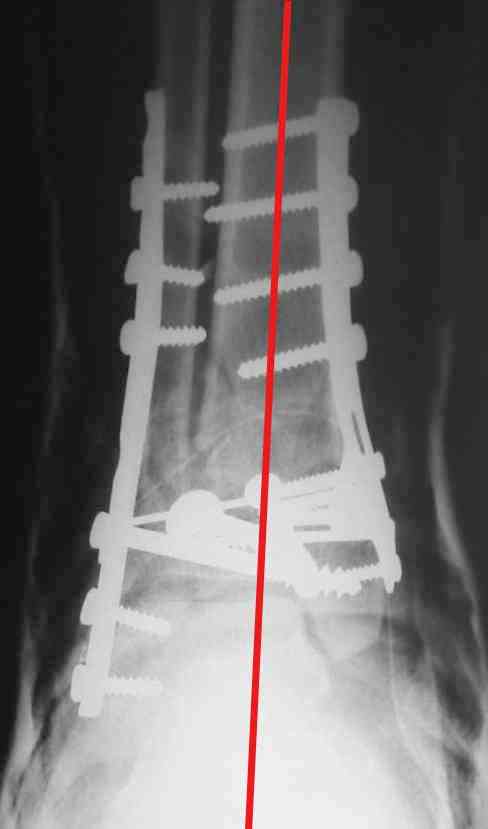

Re: Perelom N/3 kostei goleny

ДВ> Очень прилично получилось, но мне показалось, что винты на 4,5 мм.Это

ДВ> принципиально винты используются 3,5 и 4,0 мм.

На представленном снимке видно, что эпифиз смещен латерально.

Сейчас с этим ничего не сделать, похоже.